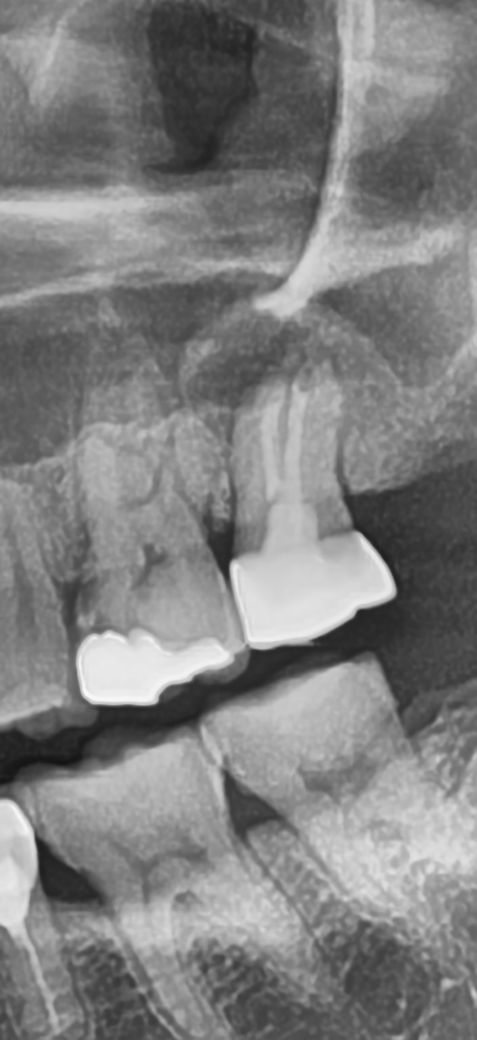

엑스레이상으로 충치가 확인되나요?

끝에서 2번째 치아

크라운한 지 10년 넘었고 최근 아플때도 있고 아닐 때도 있는데 병원마다 진단이 달라서 여쭤봅니다.

끝에서 2번째 치아에 충치가 있습니다. 다만 해당 부위의 충치는 치료하기가 매우 어려우며 잇몸 아래 그리고 뼈 바로 위에 있어 치료가 어려울 수 있습니다. 이러한 경우라면 사용할때까지 사용하고 추후 임플란트 등의 치료를 해야할 수도 있습니다.

질문하신 치아 보철물 하방으로 이차충치로 의심되는 방사선투과상이 조금 보이는 듯 하나, 정확한 진단을 위해서는 치근단방사선사진 촬영 및 임상검사까지 해보아야합니다.

크라운을 한 치아의 충치는 보통 트라우의 경기 부에서 시작하게 됩니다. 사진으로 봤을 경우 크라운의 경계 부위가 어둡게 보이긴 하지만 충치라고 단정하기는 어렵습니다.

왼쪽 끝에서 두번째 치아는 크라운은 아니고 인레이로 떼운 치아입니다

인레이 하방 약간의 충치 소견이 보이나 확정적이진 않습니다

엑스레이 상으로 보면 위쪽 뒤에서 두번째 치아 사이에 충치가 잇어 보입니다. 치료를 하시는게 좋을것같습니다.